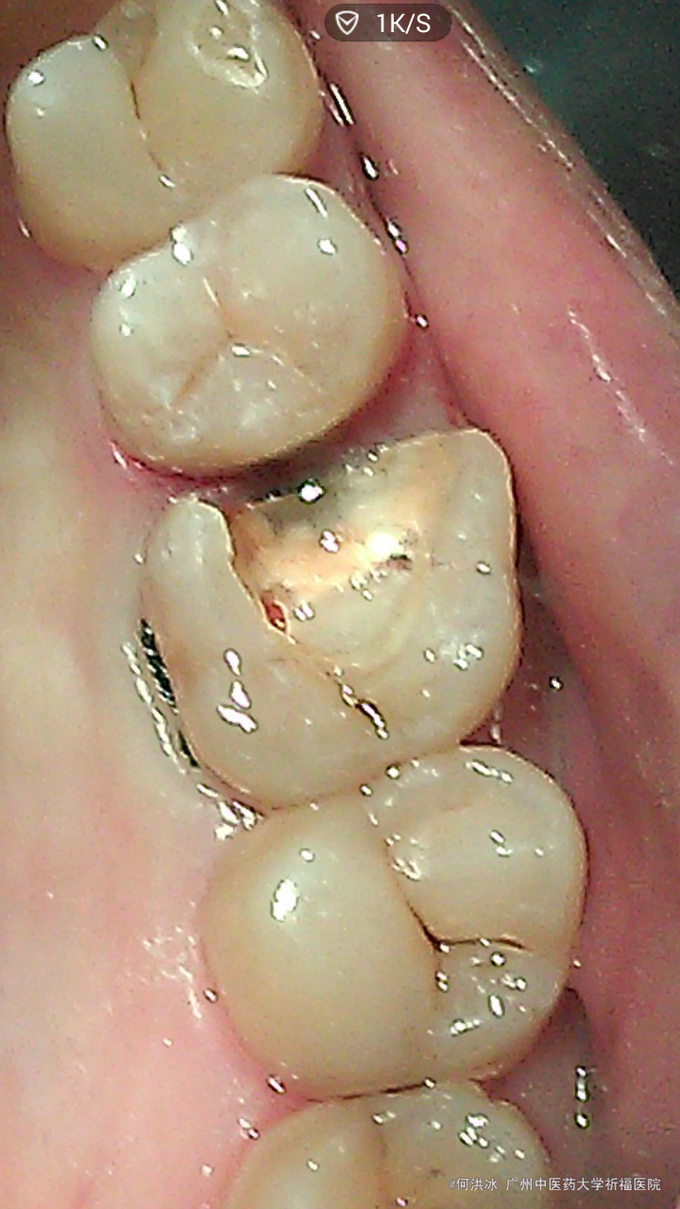

主诉:要求补牙。 病史:女,31岁。右上后牙大牙几年前在外院已做“根管治疗”,当时医生建议做冠,没同意。一直无不适,近日原充填物脱落,进食后易塞食物,要求重补。特别强调,还是不要做冠,不想磨牙太多。

查:16残冠,玻璃粘固粉充填,近中部分脱落,邻接关系不良,有食物嵌入,近中龈乳头轻度压迫性萎缩,轻度充血、红肿。根尖片示根管治疗质量可,根尖区无异常。咬合关系检查,16颊侧微倾,颊侧倒凹较大,颈部有楔缺,部分牙龈萎缩。